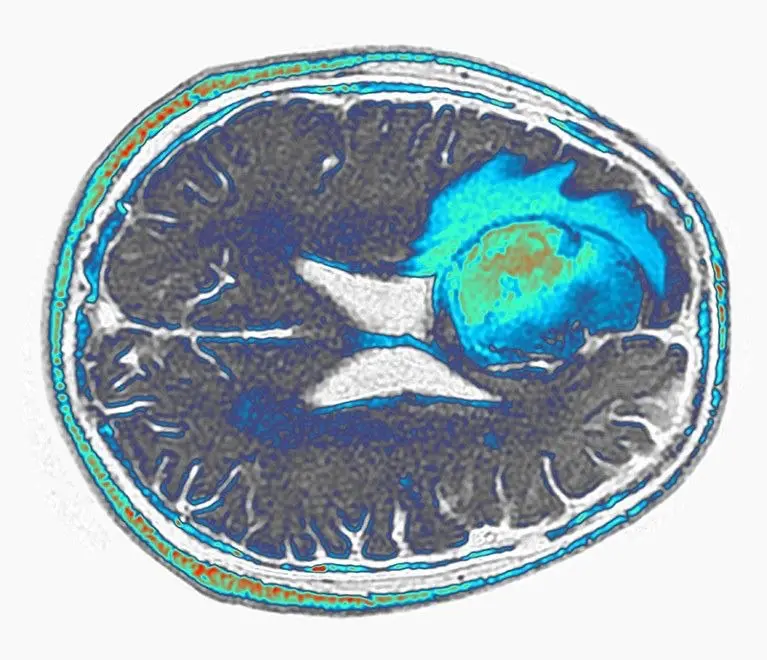

難治性脳腫瘍に対するCAR-T療法